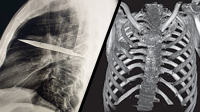

Cuando los médicos examinaron al paciente, observaron que la parte frontal del tórax derecho estaba hundida y que ese lado no se expandía del todo al respirar. Una radiografía reveló la impactante verdad: había «un objeto metálico retenido» dentro de su tórax.

La tomografía computarizada confirmó los detalles: una hoja completa de cuchillo atravesaba su cavidad torácica.

Había entrado por la espalda, cerca de la escápula derecha, deslizándose entre la quinta y sexta costilla, y su punta se encontraba entre la tercera y cuarta costilla del frente. El arma estaba rodeada de pus y tejido necrótico, y las imágenes mostraron fracturas ya curadas en la escápula y varias costillas.